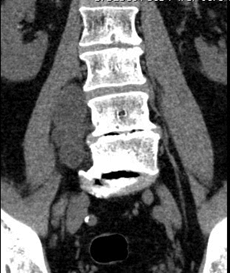

In January 2020, a pelvis CT study of the lumbosacral region revealed multiple hypodense paravertebral formations, referable to joint cysts (Figures 1 & 2). F18G-PET showed a hypermetabolic area (SUV max 3.0) on the right paravertebral muscles at L5-S1 level deepening into the right psoas major muscle.

Figure 1: Coronal CT scan of lumbosacral spine.